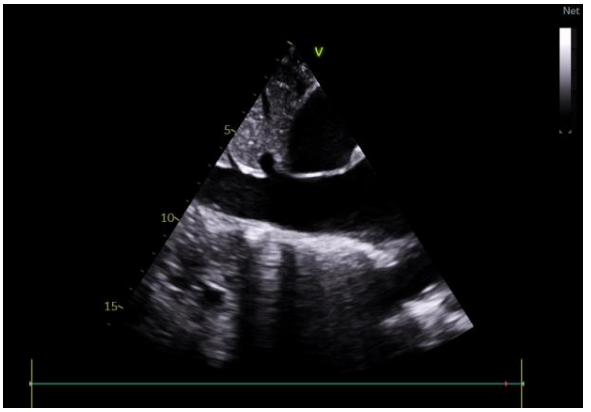

The electrocardiogram showed peripheral microvoltage and right bundle branch block (figure 1).

Figure 1: diffuse low voltage with right bundle branch block